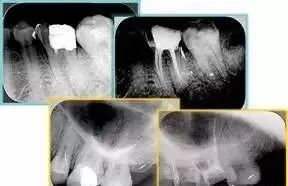

左图为根管充填术后 X 线片。图中可见,根管充填较好。右下图有白色小点,为侧方加压导致糊剂挤出所致,表明根管充填比较致密。

致密、恰到好处的充填可去除干净根管里感染灶,机体逐渐恢复。

多根牙时候需进行偏移投照,正位投照无法说明具体哪根牙根管充填效果。